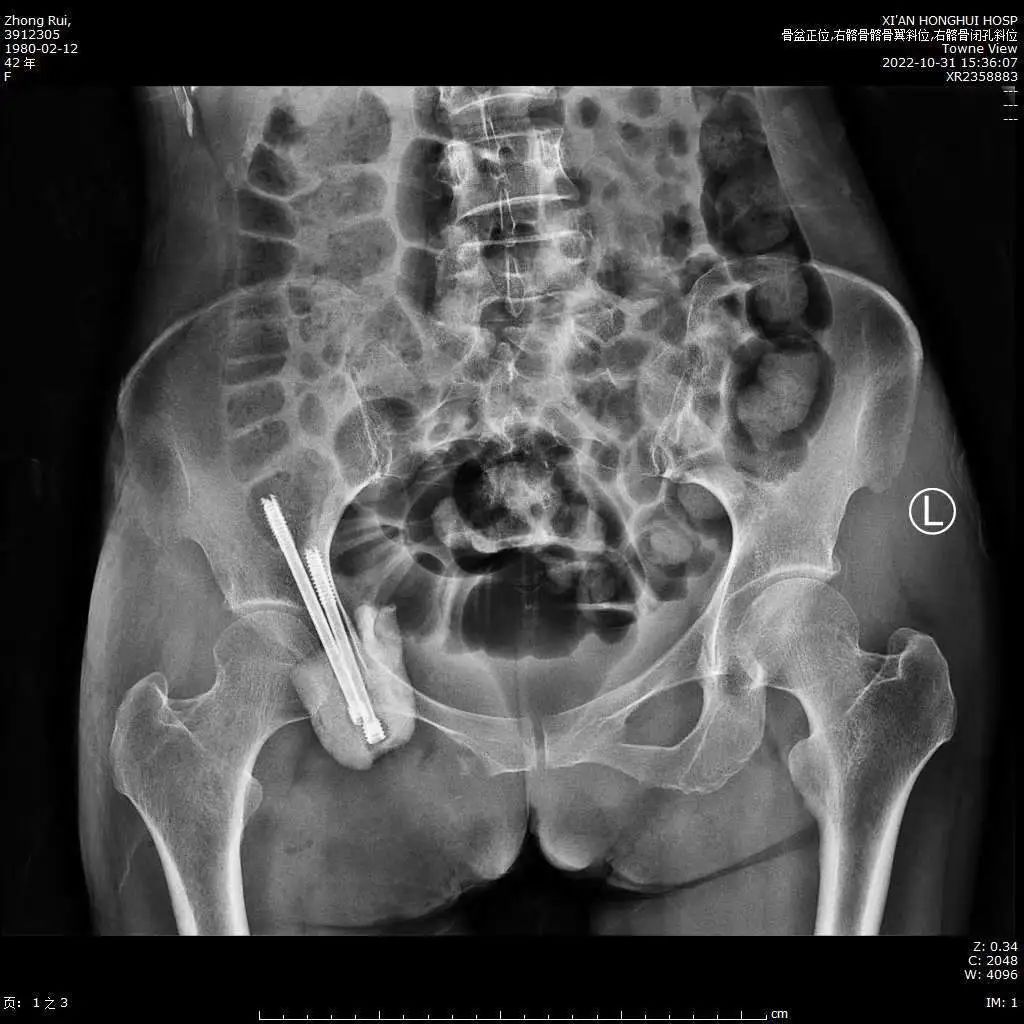

术后患者的下肢神经功能无损伤,经过改善贫血、纠正低蛋白,患者大小便功能逐步恢复,王女士康复良好,对手术疗效表示十分满意。

(术后X线显示髋臼周围重建良好)

(髋臼周围瘤体切除术后重建影像资料)